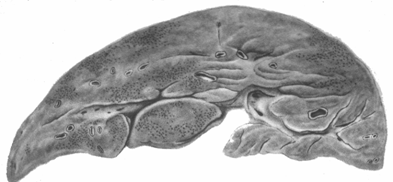

М

орфологическим

своеобразием отличается Б. б. у

новорожденных, возникающая в результате

трансплацентарной передачи вируса

плоду от беременной больной или

вирусоносительницы. Своеобразие это

заключается в присутствии многоядерных

гигантских клеток типа симпластов,

встречающихся при вирусном гепатите

также у детей раннего возраста (рис. 3),

В

Рис. 3. Затяжная форма болезни Боткина (мальчик 1 года 8 мес.) Гигантоклеточный метаморфоз печеночных клеток.

небольшом проценте случаев обычное течение Б. б. осложняется массивным некрозом печеночных клеток, что сопровождается клинической картиной острой недостаточности печени и квалифицируется анатомически как острая токсическая дистрофия печени или острая атрофия. Отмечаемые макроскопически дряблость печени и уменьшение ее размеров (рис. см. отд. табл., рис. 3) зависят но только от гибели паренхимы, но и от уменьшения кровенаполнения в спавшейся строме. При более медленном развитии некрозов — при подострой дистрофии печени — на фоне большой убыли паренхимы и воспалительных инфильтратов четко выступают процессы регенерации и некоторая коллагенизация стромы, что обусловливает более плотную консистенцию печени. Исход острой и подострой дистрофии печени — летальный или в узловую гиперплазию с рубцеванием, или в постнекротический цирроз печени.Из внепеченочных изменений, наблюдаемых при острой и подострой дистрофии печени, осложняющих Б. б., наблюдаются: в мозгу резкие пиркуляторные нарушения, тяжелые дистрофические изменения нервных клеток; в почках — дистрофические изменения, доходящие до некротического нефроза; острые некрозы в поджелудочной железе; геморрагический диатез; нередко асцит в сочетании с отеками; гиперплазия портальных лимфатических узлов и селезенки с миелозом пульпы; дистрофия мышцы сердца; умеренный глыбчатый распад волокон поперечноисчерченных мышц (особенно икроножных).